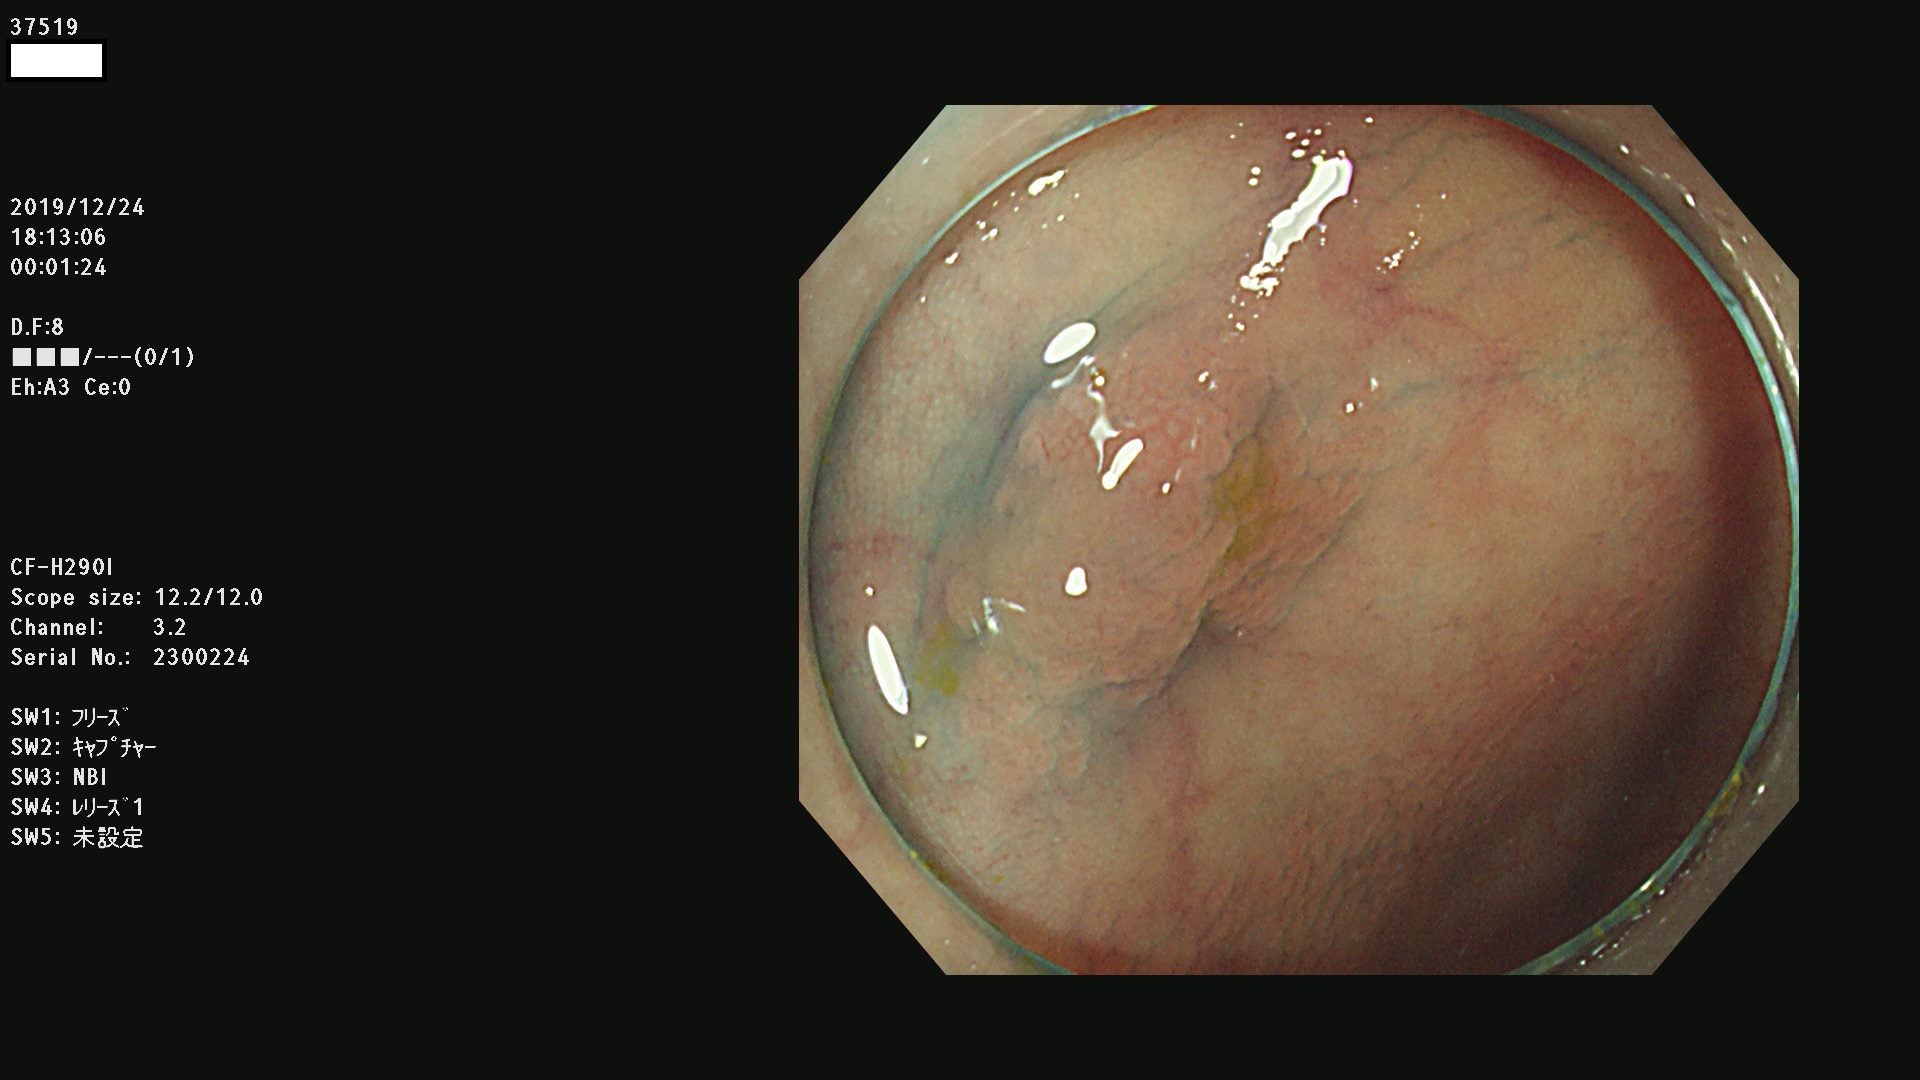

発見困難で危険性の高い平坦型病変(上記100名より抽出) ![]()